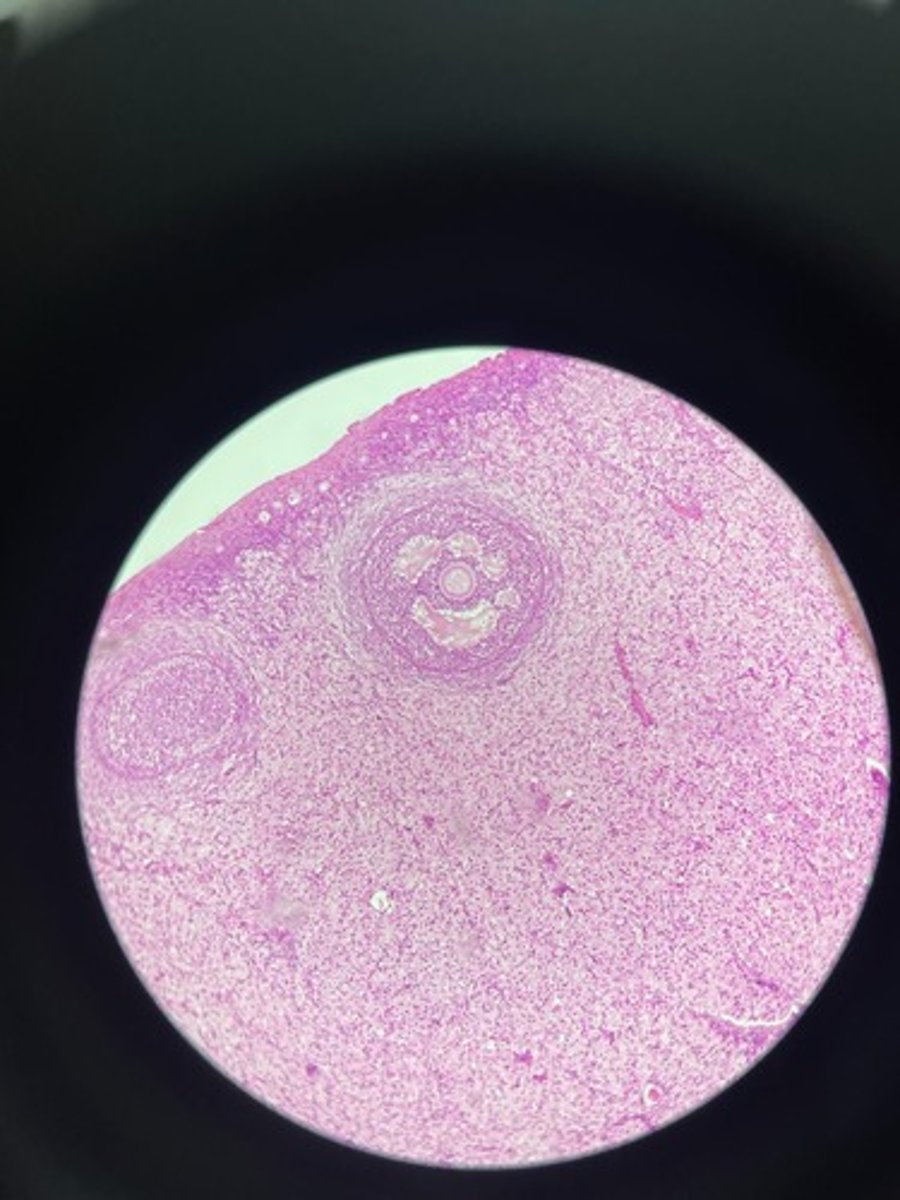

Lymph node HE

Lymph node HE

Lymph node HE

lymph node HE

Lymph node HE

Lymph nodes HE